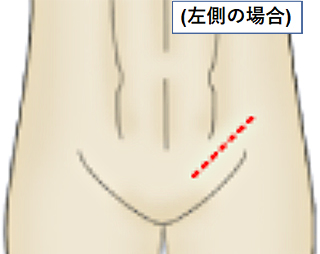

そのため、摘出する側の下腹部の鼠径部を切って手術を行います。この手術方式を高位精巣摘除術といいます。

皮膚切開の部位